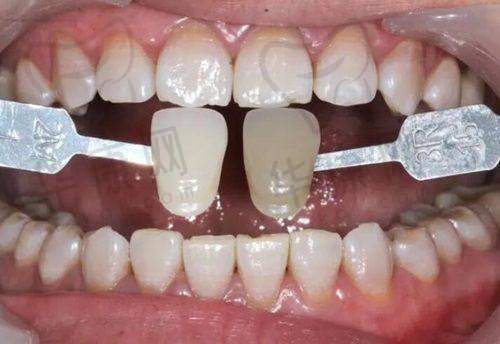

多年来,云南昆明竹子口腔医院在儿童早期矫正方面积累了众多成功实例。许多原本存在牙齿不齐、咬合不正等问题的孩子,在经过该医院的矫正治疗后,牙齿变得整齐美观,面部轮廓也得到了改善。这些成功实例不仅体现了医院的技术实力,也赢得了家长们的广泛好评。在口碑方面,医院以优质的服务和良好的治疗成效,在昆明地区树立了良好的形象。家长们对医院的医生专精度、服务态度以及价格合理性都给予了高度评价。特别多家长表示,选择云南昆明竹子口腔医院为孩子进行早期矫正,是一个非常正确的决定。